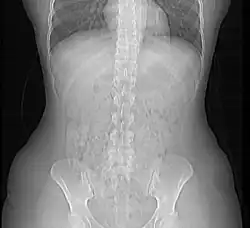

Das Bild rechts basiert auf einer DICOM-Datei. Zur Anzeige wurde es in ein Standard-Grafikformat konvertiert.